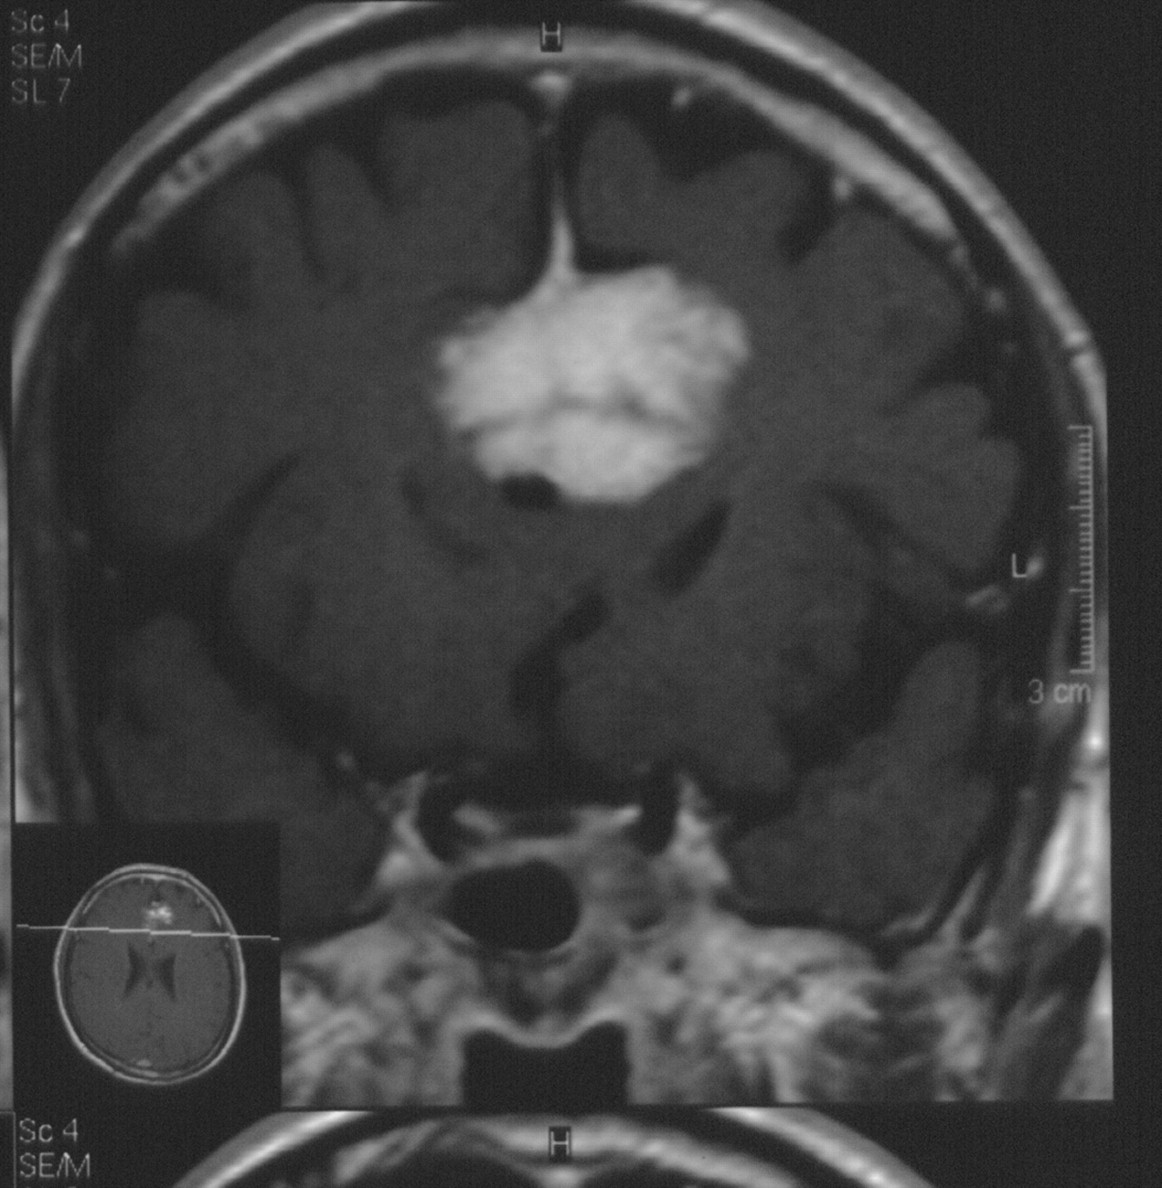

左小脑占位,是否有明显尾征,能确定小脑幕脑膜瘤么

图片尺寸2501x1840